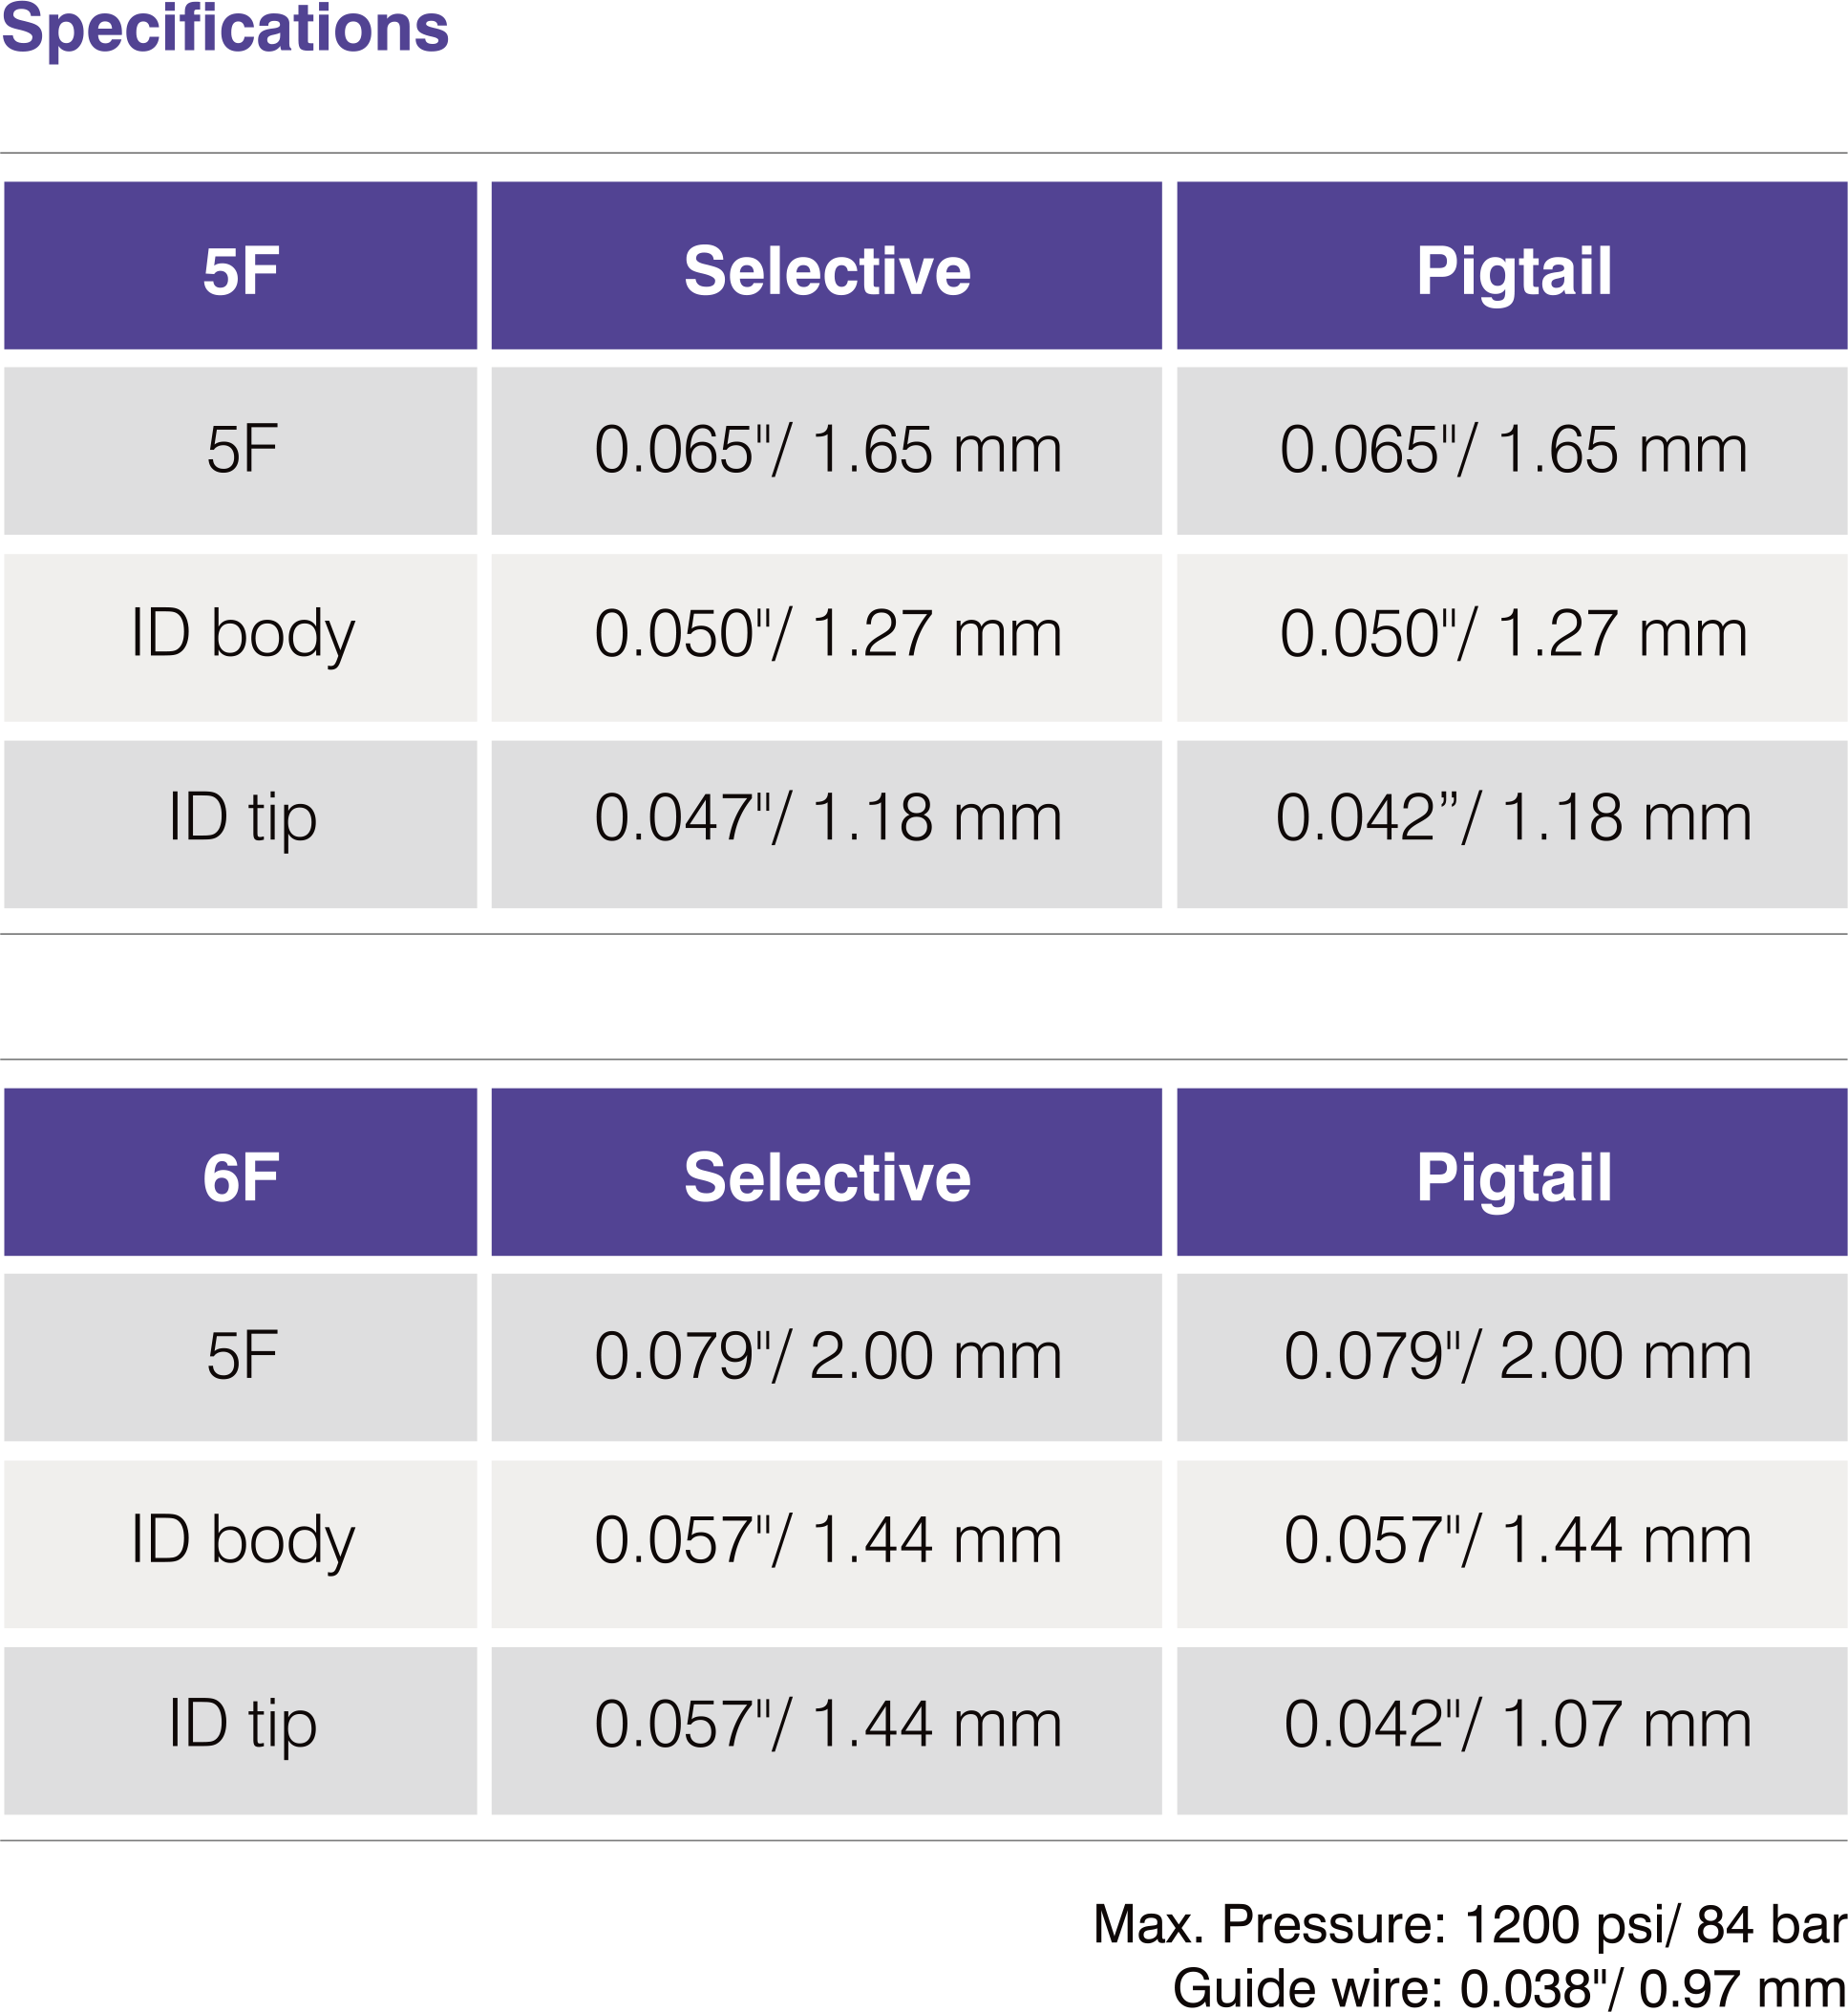

Radial Diagnostic Catheter

Features & Benefits

-

Enables angiography of both RCA and LCA with one catheter that can potentially:

• Eliminates a catheter exchange step

• Shorten procedure & fluoroscopic time

• Lower cost per procedure - Engages with simple clockwise & counter clockwise rotation

- Soft tip reduces potential for vessel trauma

- High Flexibility

- Superior Surface Smoothness

- Excellent 1:1 Torque Control due to double wire stainless steel braiding

- Large inner lumen for superior flow rates

- Atraumatic soft tip

- Guidewire Compatibility : 0.038”/ 0.97mm

- Max Pressure : 1200 PSI / 84 bar